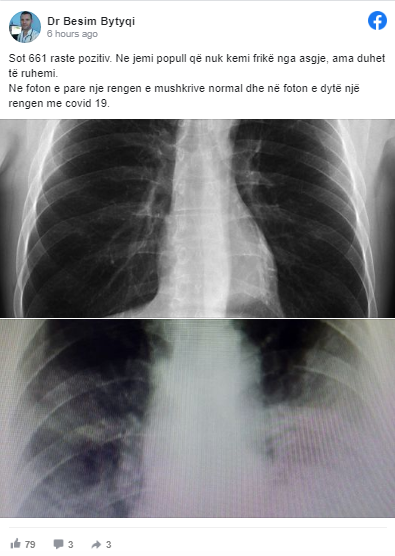

“Sot 661 raste pozitiv. Ne jemi popull që nuk kemi frikë nga asgjë, ama duhet të ruhemi. Në foton e parë një rengen e mushkërive normal dhe në foton e dytë një rengen me covid 19”, ka shkruar ai.